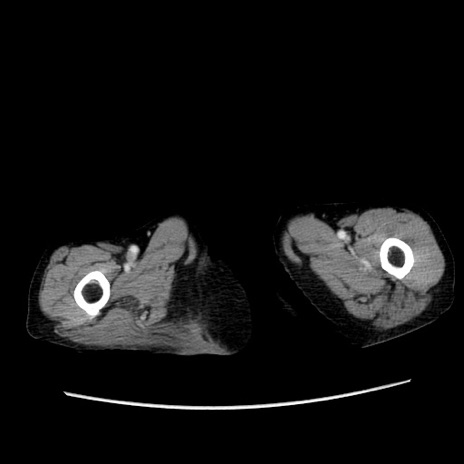

症例25(横断像)

【症例】80歳代女性

【主訴】胸のつかえ感

【現病歴】約9時間前に食後から胸のつかえた感じあり、嘔吐あり、来院。

【既往歴】胃癌(全摘)、胆摘、虫垂炎

【身体所見】心窩部に圧痛あり、反跳痛なし。

【データ】WBC 5700、CRP 0.05